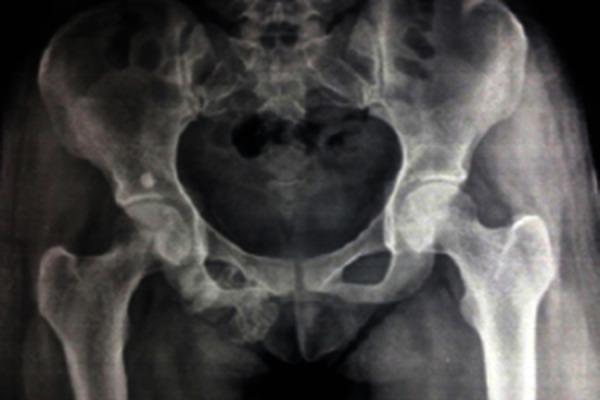

We present a case of 18 year female, who came with a swelling in right groin since 2 years which was diagnosed to be osteochondroma on x-ray and magnetic resonance imaging. Excision biopsy was done as the patient wanted it to be removed for cosmetic purpose and confirmed it to be non-malignant osteochondroma. There has been no recurrence even after 1 year of follow up.

我们报告一例18岁女性病例,该患者自两年前起右腹股沟出现肿胀,经X线和磁共振成像诊断为骨软骨瘤。由于患者出于美容目的希望切除,遂进行了切除活检,结果证实为非恶性骨软骨瘤。随访1年,未见复发。